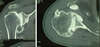

Les radios standards confirment la présence d’une arthrose centrée (sans rupture de la coiffe).

Il faut demander un arthroscanner qui confirmera l’importance de l’usure cartilagineuse et osseuse, et la bonne continuité de la coiffe.

Arthroscanner d’épaule

Prothèse totale d’épaule anatomique